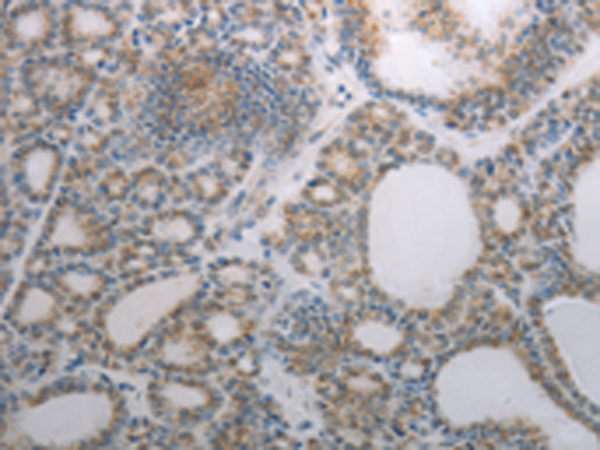

分类: 科研抗体货号: P11119别名: NPTIIb, NAPI-3B, NAPI-IIb应用: IHC反应种属: Human